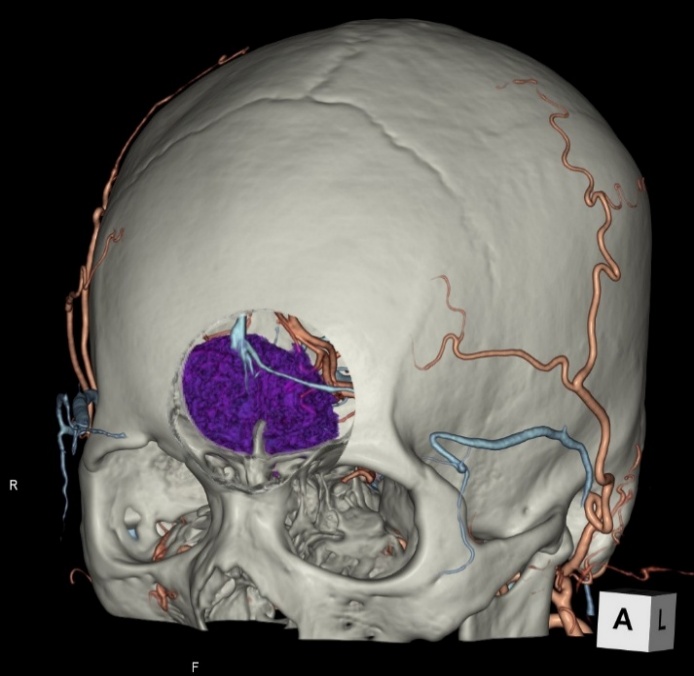

画像診断装置・放射線治療装置紹介

X線CT装置

64列 MDCT Aquilion CX (canon)

|

80列 MDCT Aquilion PRIME (canon)

80列 MDCT Aquilion PRIME SP(canon)

大きなトンネルの中に体を入れて、X線をあてて体の輪切りの写真を撮ります。CT検査には、単純CT検査と、造影剤を注射して撮影する造影CT検査があります。